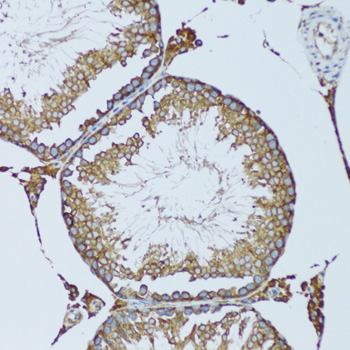

Immunohistochemistry of paraffin-embedded mouse testis using RPN1 at dilution of 1:100 (20x lens).